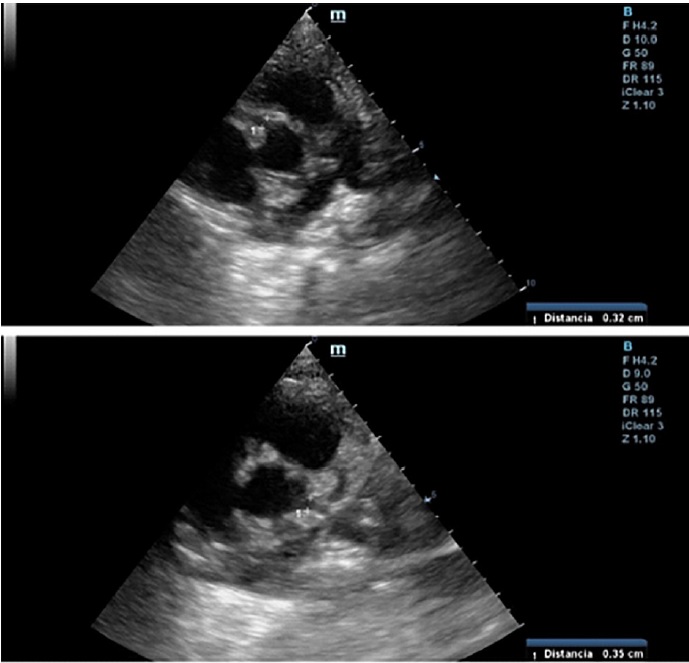

Within 24 hours from discharge, the patient had fever, poor general condition, raspberry tongue, bilateral palpebral edema, and conjunctivitis. The patient was hospitalized. Laboratory tests showed inflammation and positive SARS-CoV 2 IgG, and a repeat echo-Doppler (Figure 1) showed aneurysmal dilation in both coronary arteries with preserved ventricular function (Table 1 outlines coronary values with their corresponding Z scores upon successive echocardiography monitoring). The condition was reassessed as MIS-C. The patient received immune-mediated treatment and platelet aggregation inhibitors with gamma globulin (2 g/kg/dose), methylprednisolone (10 mg/kg/dose, 3 pulses), ASA 5 mg/kg/day. The patient showed mild clinical and analytical improvement. Heart monitoring after 5 days revealed similar characteristics. The patient was classified as treatment-resistant, and infliximab was prescribed (5 mg/kg). He showed good progression, with significant clinical and cardiovascular improvement, and was discharged after 16 days. Cardiologic and rheumatologic workup plus platelet aggregation inhibitor and anti-inflammatory therapy were scheduled.

Fig. 1 2D echo-Doppler (vessel short axis): Right coronary artery (above) and left coronary artery (below) are shown.